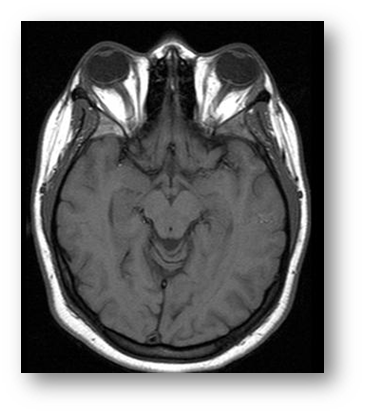

- FUSIÓ DE LA IMATGE: amb visió binocular el cervell rep la informació de dues imatges lleugerament diferents per la posició dels ulls. El cervell reconstrueix les imatges en una de sola.

L'ull esquerre, a través d'un filtre verd, només veu el rectangle verd, mentre que l'ull dret, a través d'un filtre vermell, només veu el punt vermell.

Atès que cada imatge es veu independentment de l'altra (dissociació d'imatges), els ulls es col·loquen en posició de descans fisiològic. El punt sembla estar desplaçat. El desplaçament del punt respecte al rectangle és proporcional a l'angle dels eixos visuals en posició de descans fisiològic.

Si el punt es troba dins del rectangle o sobre el rectangle, la persona té un comportament visual normal.

Si el punt surt del rectangle, tal vegada no hi ha bona fusió i es pot generar fatiga visual.